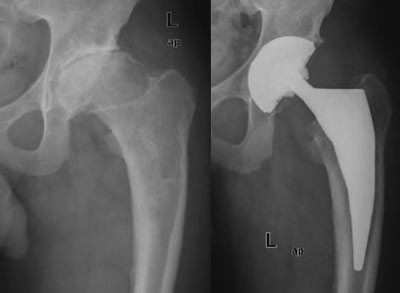

Harris’ hofteskår ble målt preoperativt og postoperativt etter ett år. Gjennomsnittlig skår preoperativt var 49 (spredning 27 – 66) og postoperativt 97 (spredning 76 – 100). Preoperativt var det aktuelle bein kortere (1 – 3 cm) hos 20 pasienter. Postoperativt var beina like lange hos 35 pasienter, hos én pasient var beinet fortsatt 1 cm for kort, og hos én pasient var beinet blitt 1 cm for langt (overkorreksjon). Eksempler på bruk av den individtilpassede hofteprotesen fremgår av figur 6, figur 7 og e-figur 8.